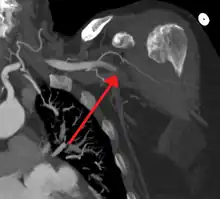

Acute occlusion of the axillary artery resulting in an ischemic limb as seen on CT angiography

Once signs and symptoms of acute limb ischemia are identified, the cause and location of the occlusion and its severity need to be addressed. A clinical pulse examination can be done to detect the location of the occlusion by finding the area where the pulse is detected until the area where the pulse disappears. The skin temperature would also be colder in the pulseless area when compared to the area where the pulse is present.[1]

A Doppler evaluation is used to show the extent and severity of the ischaemia by showing flow in smaller arteries. Other diagnostical tools are duplex ultrasonography, computed tomography angiography (CTA), and magnetic resonance angiography (MRA). The CTA and MRA are used most often because the duplex ultrasonography although non-invasive is not precise in planning revascularization. CTA uses radiation and may not pick up on vessels for revascularization that are distal to the occlusion, but it is much quicker than MRA.[1] In treating acute limb ischaemia time is everything.[16]